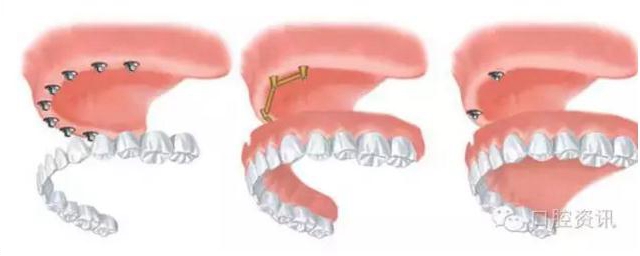

圖6. 全口牙齒缺失種植治療的各種選擇((1) 固定式(2) 桿卡式可摘義齒(3)球帽式可摘義齒)

2 . 牙支持式固定義齒